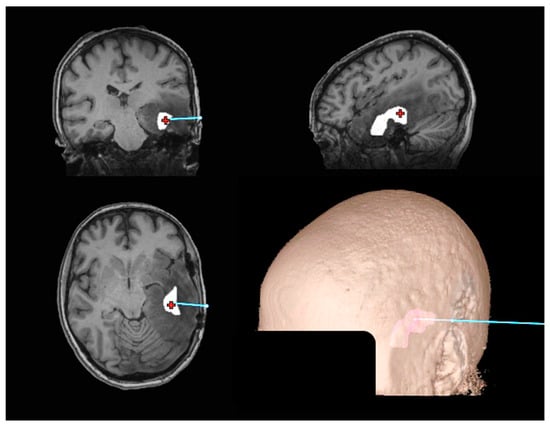

2.1. Stereotactic Biopsy